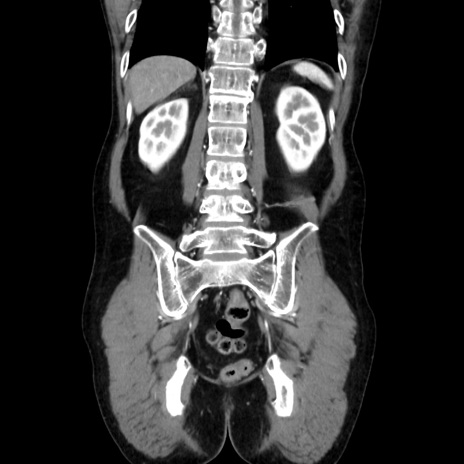

症例37(冠状断像)

【症例】40歳代 男性

【主訴】腹痛

【現病歴】4時間ほど前に電車に乗車中に臍部上より腹痛出現。徐々に増悪し起立困難となり、救急外来受診。生ものは数日食べていない。今朝お雑煮を食べた。

【身体所見】BT 36.8℃、BP 117/84mmHg、HR 91/min、SpO2 97%、苦悶様、腹部:臍上部広範囲圧痛あり、反跳痛±

【データ】WBC 8100、CRP 0.03